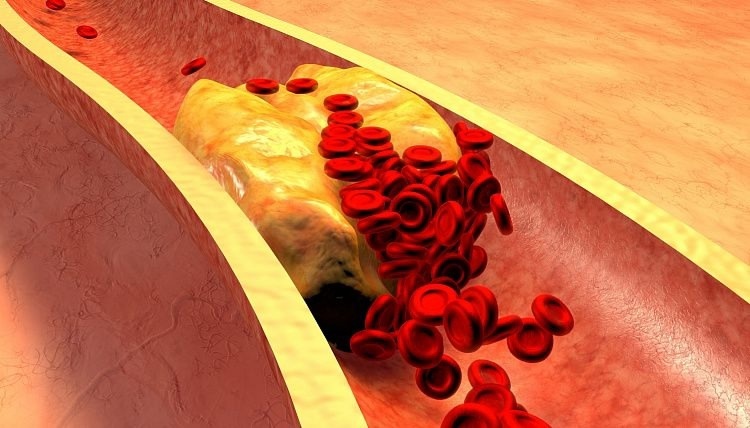

Итак, для начала надо разобраться с терминами в названии. Синдром жировой эмболии – это закупорка кровеносных сосудов жировыми капельками (глобулами). Если такая капелька встаёт поперёк сосуда, она именуется отдельным термином – эмбола. Как эти капельки появляются – отдельный вопрос, об этом будут душные параграфы ниже. И вот двигается такая капля-путешественница по организму сливается с похожими каплями, постепенно укрупняясь. Достигая размера больше эритроцита (примерно больше 7-8 мкм) капли начинают закрывать просвет капилляров. Ситуация в принципе напоминает ту, при которой ты пытаешься пропихнуть пузырёк воздуха в пипетке, а он не идёт, зараза такая. Только в данном случае исполняют жиры. Так же эта капелька может налипнуть на стенку сосуда, обрасти форменными элементами крови и вырасти в полноценный тромб. Закупорив сосуд, эта глобула или тромб мешают кровотоку, что приводит к ишемии (кислородному голоданию) органа ну или инфаркту (а это уже смерть), если ишемия зашла слишком далеко. Если такое состояние затронет один или несколько жизненно важных органов – произойдет смерть всего организма.

По сути – продолжение механической. По её концепции жир из перелома попадая в кровоток, активирует фермент под названием липаза (расщепляющий жир). Видов липаз существует множество и некоторые из них даже путешествуют по кровотоку. Вот только вдобавок к расщеплению жиров высокий уровень липазы вызывает слипание хиломикронов (молекулы холестерина низкой плотности. Он хороший, качественный и вообще – друг человека). Потом всё это налипает на стенки сосудов, вызывает атеросклероз, тромбоз, а уже они собсна вызывает симптоматику которую мы и наблюдаем. Как можно заметить в этой теории основной упор делается на атеросклероз с тромбами, а наличие жировых эмбол – только триггер изменений. А так как весь этот механизм требует времени на развёртывание – как раз укладываемся в пролаг нескольких дней. И вот вроде всё хорошо, всё выяснили, да только, согласно этой гипотезе, реакция эта системная и происходить должна сразу во всём организме. А на деле у нас есть чёткое разделение: сначала круг малый, потом большой. Значит снова неувязочка. Едем дальше